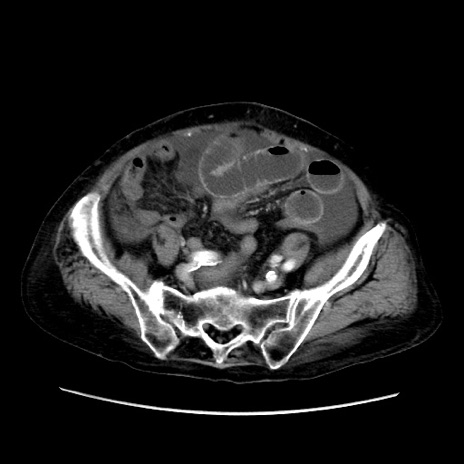

症例31(横断像)

【症例】80歳代 女性

【主訴】腹部膨満感

【現病歴】他院にて肝硬変にてフォロー中。1週間前から便秘、腹部膨満感、臍部腫瘤あり受診となる。

【既往歴】肝硬変

【身体所見】腹部膨隆あり、皮膚変化なし、疼痛なし。

【データ】WBC 4600、CRP 0.25